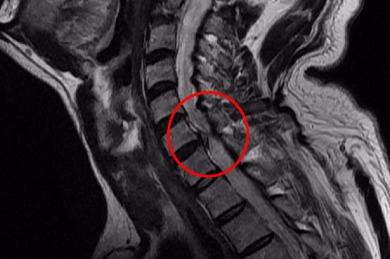

우선 목디스크란 목뼈 사이의 디스크가 손상되어 발생하는 질환을 의미합니다. 디스크는 척추뼈 사이에서 충격을 흡수하고 신경을 보호하는 역할을 하는데, 디스크가 손상되면 신경이 압박되어 통증, 저림, 마비 등의 증상이 나타납니다.

목디스크의 원인은 다양하지만, 가장 흔한 원인은 외상입니다. 외상은 교통사고, 스포츠 부상, 낙상 등 다양한 원인으로 발생할 수 있습니다. 또한, 잘못된 자세, 과도한 스트레스, 노화 등이 목디스크의 발생 위험을 높입니다.

하지만 증상이 심하지 않은 경우, 보존적 치료를 통해 호전될 수 있습니다. 보존적 치료에는 휴식, 약물치료, 물리치료, 운동치료 등이 있습니다. 그러나 증상이 심한 경우에는 수술이 필요할 수 있습니다.